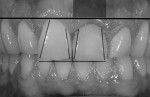

Intraoral photographs revealed details to help the dental team create a greatly enhanced restoration. The patient never mentioned a problem with the color of the restoration; his primary concerns centered on contour, form, and the disharmony created by the less than perfect restoration. Taking this into account, the color intraoral photographs were converted to black and white, which would allow the dental team to assess the patient’s concerns (Figure 2). The black-and-white image showed that the restoration did not have the same form as the patient’s natural dentition. Graying under the tissue from the metal abutment, an obvious tissue-level discrepancy, was also noted.